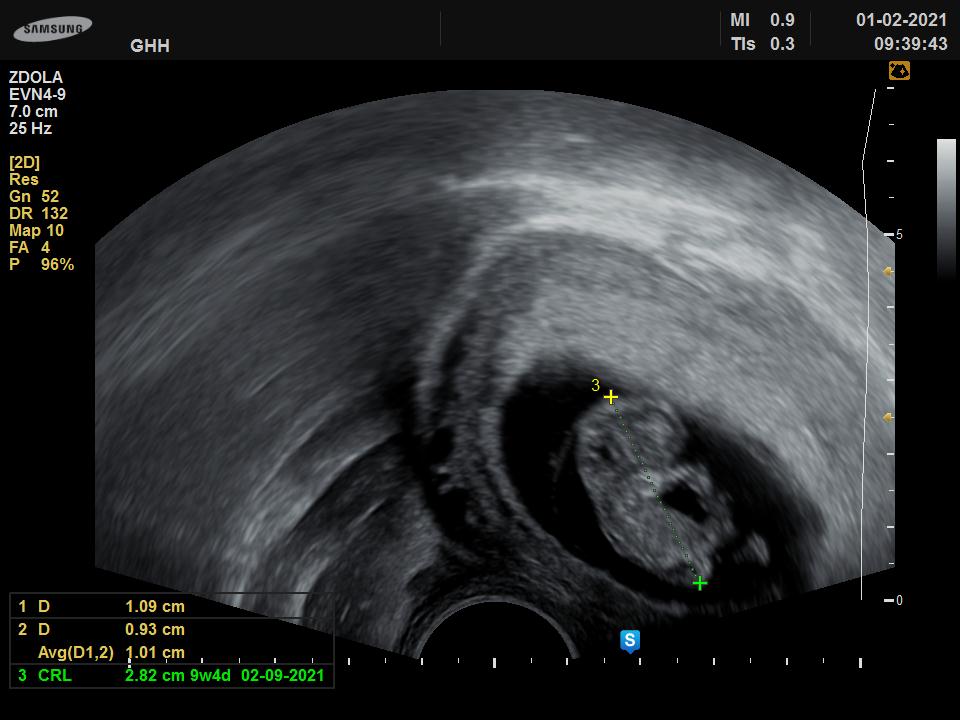

Ahoj holky, tak miminko je zatim ukazkove ❤ odpovida presne tydnu a dni. Uz mam prukazku, za 3 tydny velky screening. Uz ma krasne nozicky, rucicky a nadherne se hybalo a mavalo. Uplne jsem byla prekvapena, jake uz to bylo krasne miminko. Dr.rikala, ze uz je to velky bobisek ❤ posilam foto. Holky není screening v 12+5 pozdě?